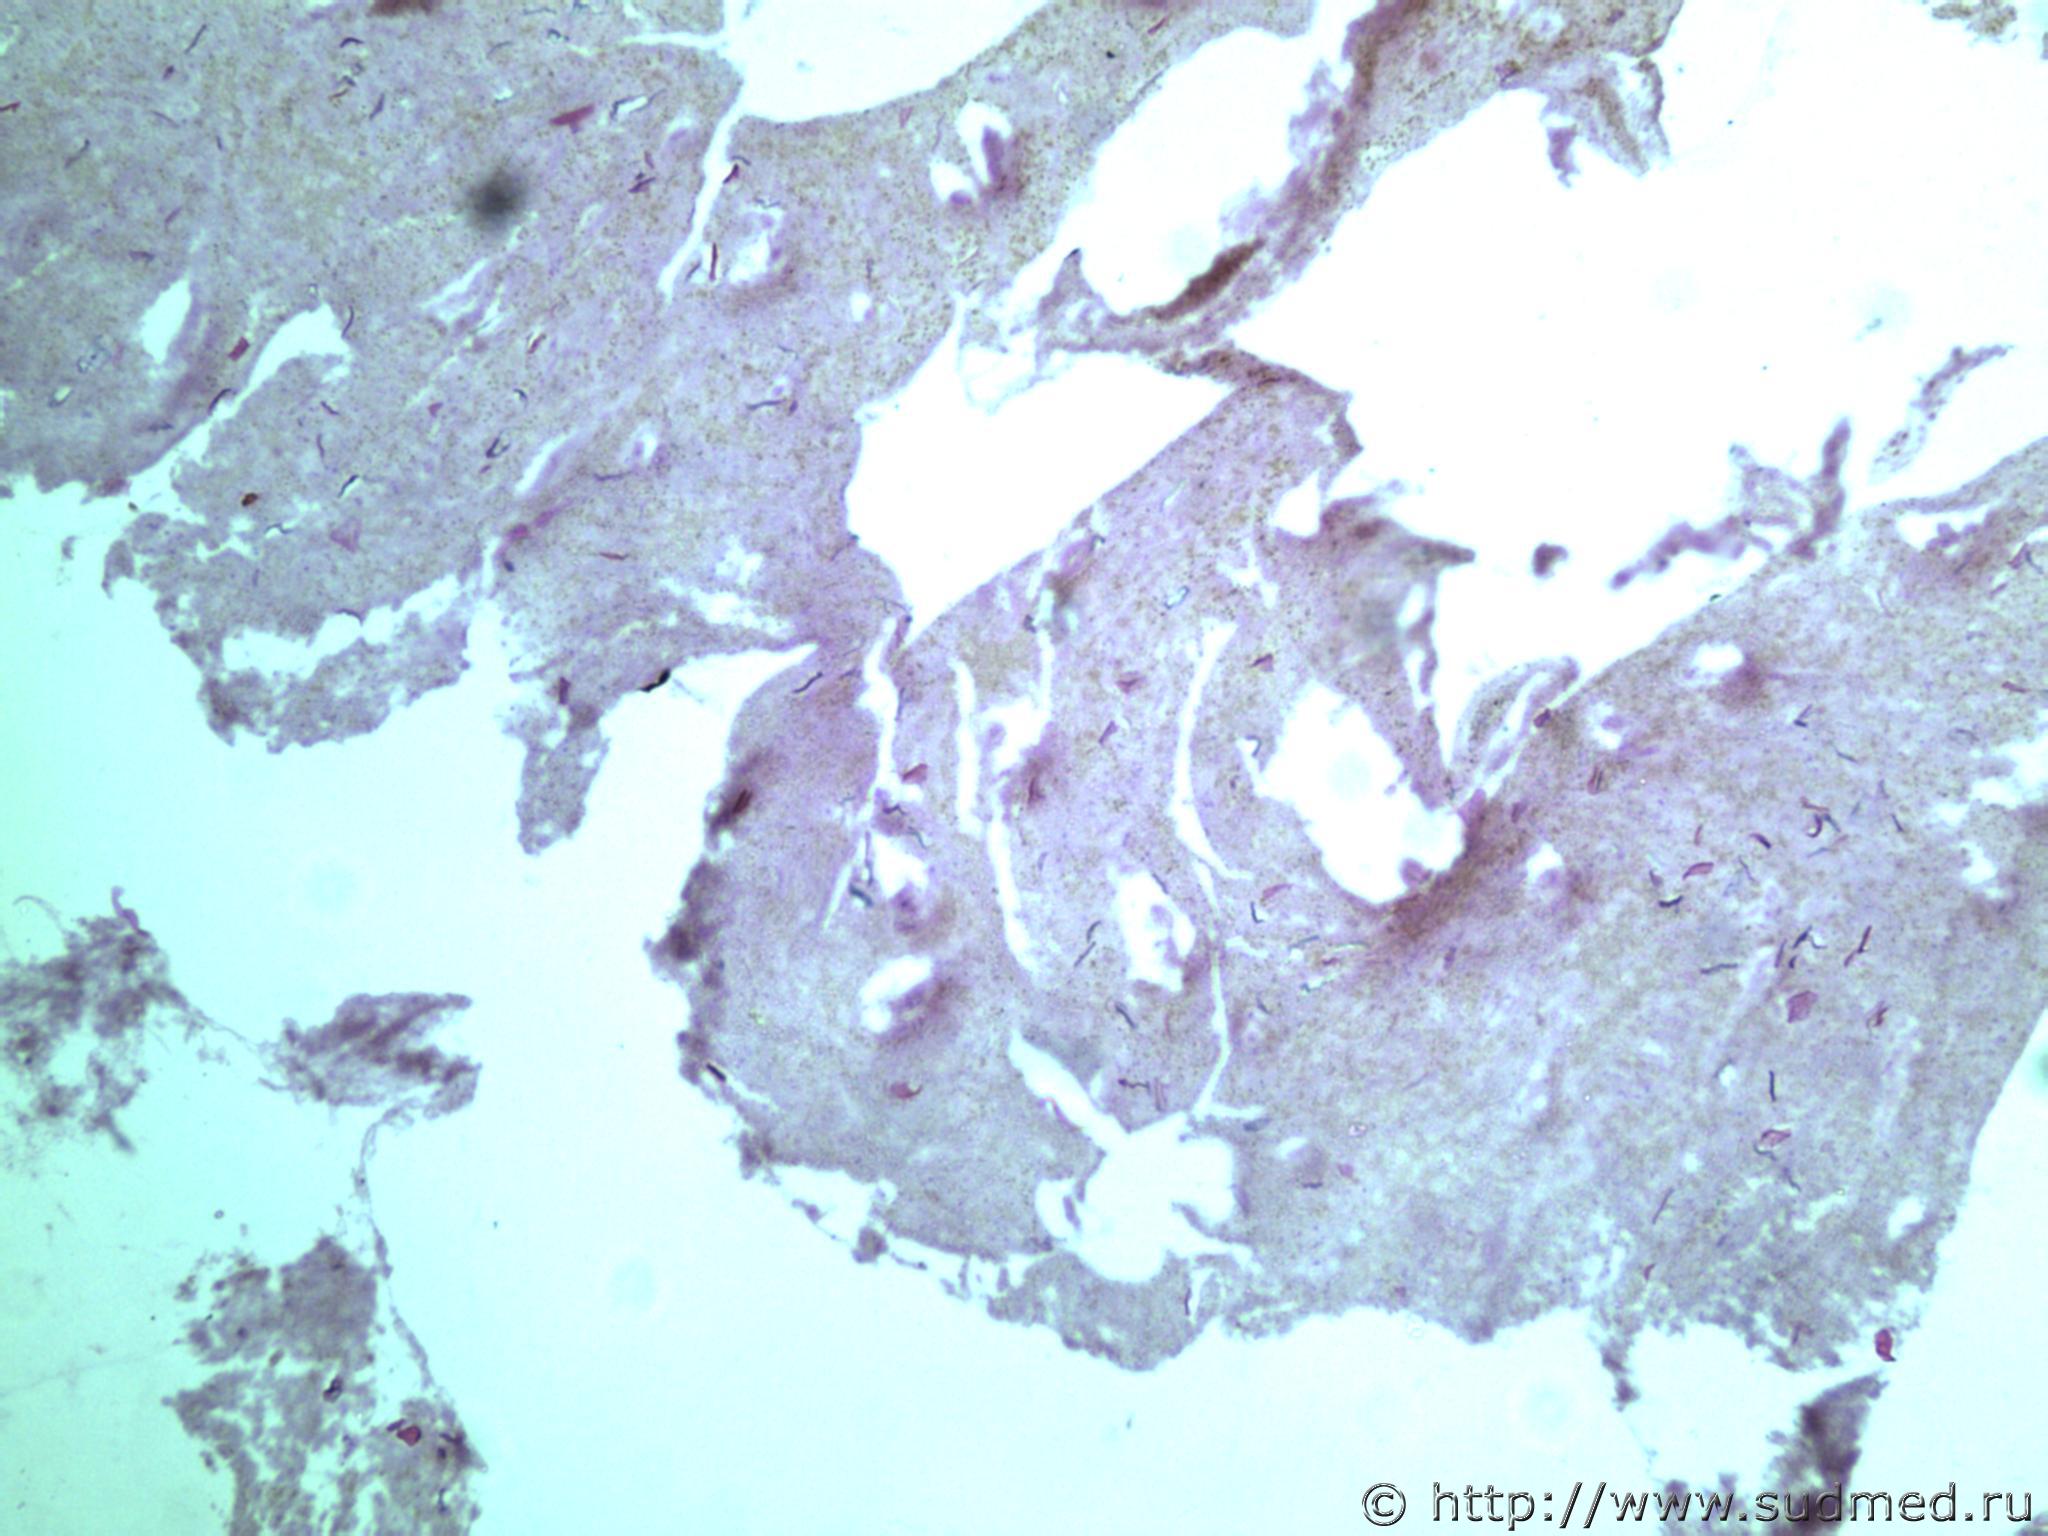

всем здравствуйте. хотела бы знать ваши мнения. провожу экспертизу. препараты как и труп новорожденного гнилые либо в аутолизе страшном. в легком картина такова, что ткань "плотная". просвет различимых альвеол в виде щелей и по всем полям зрения элементы околоплодных вод. одна артерия пуповины спазмирована. остальные сосуды непонятно : просвет их спавшийся но без признаков спазма. они как будто сплющены. да и сама пуповина в виде тонкого тяжа, видно из-за гнилостных изменений. под тмо спинного мозга признаки кровоизлияния, как и в коже с шеи. в коже головы с полнокровием отдельных сосудов. мать утверждает что ребенок после родов не сразу но все же шевелился и кричал. хотя перед этим он выпал у нее из матки на пол, ударившись головой. и со слов матери у него была пена изо рта и он хрипел.

Микрофото лёгких показать можете ?

сегодня сфоткаю конечно. но не факт что будут качественные фотки. плавательная проба - "сомнительная".

Судебная медицина - Прикрепленное изображение Судебная медицина - Прикрепленное изображениеСудебная медицина - Прикрепленное изображениеСудебная медицина - Прикрепленное изображениеСудебная медицина - Прикрепленное изображение

ну вот как то так. там еще и фотки пуповины.

Плохо,материал гнилой.

Остановился бы на дышавшем лёгком.

5 фото в сообщении №4 и 8 фото в сообщении №5 не наводит ли на мысль о дышавшем лёгком ?

Про остальные фото молчу,там или ничего не видно или же есть оптически пустые пузыри,что вероятнее всего,проявления гниения.